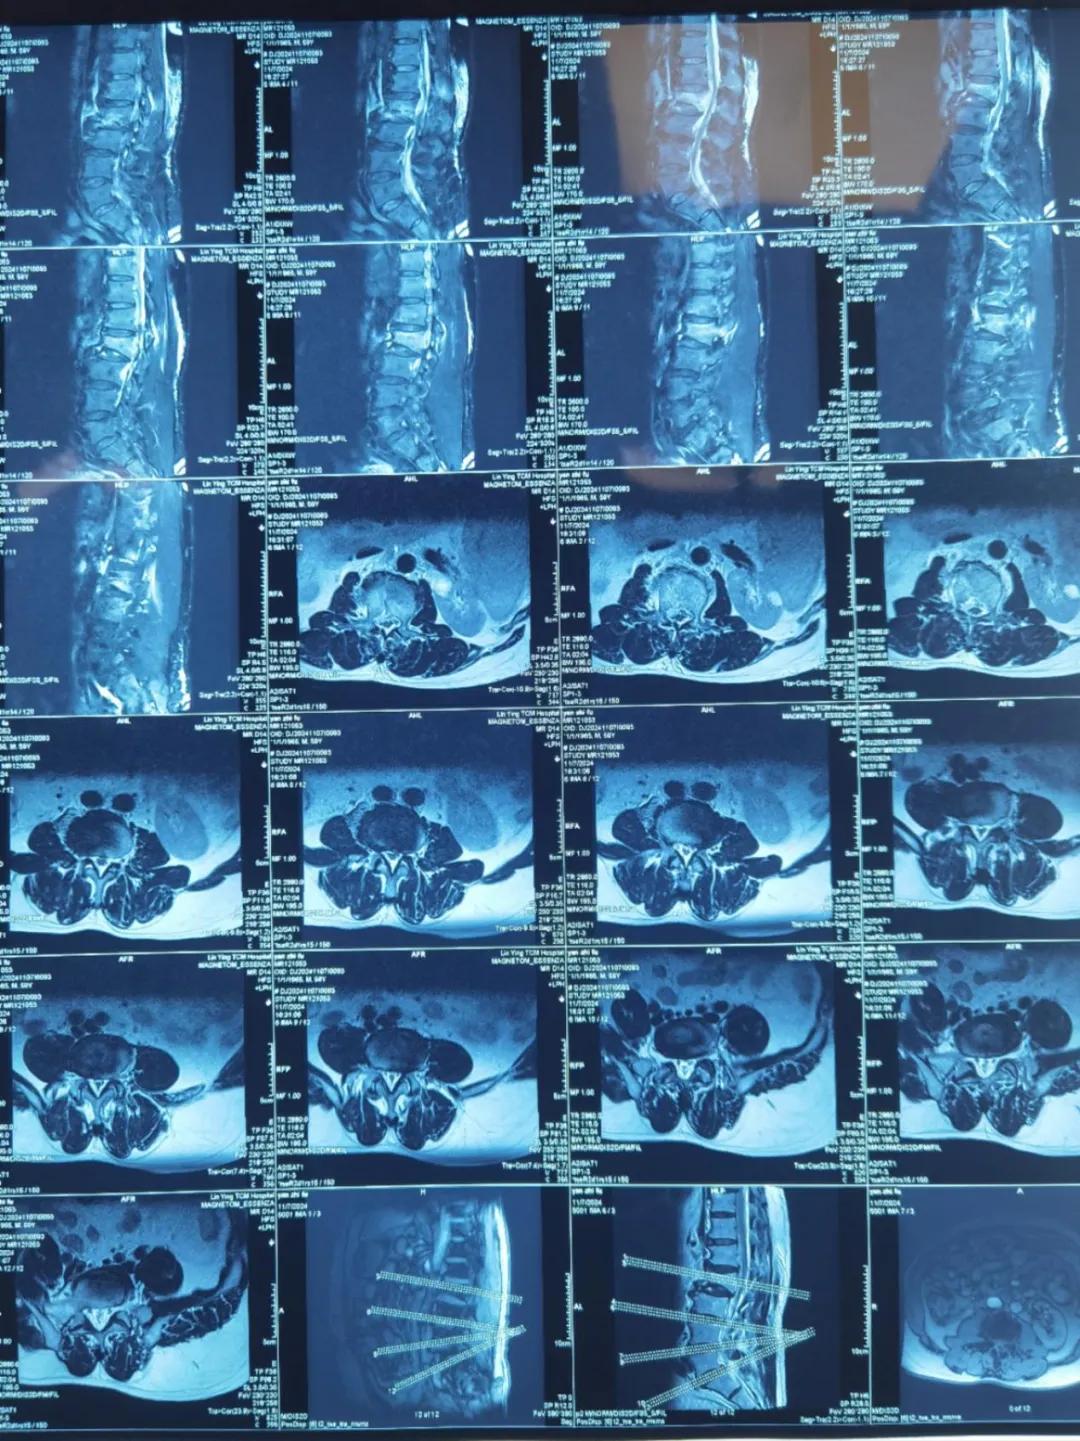

“醫(yī)生,這是之前的檢查結(jié)果,還需要再做檢查嗎?”閆大叔從外院轉(zhuǎn)來被推進(jìn)智能微創(chuàng)骨科。幾天前,他在老家的中醫(yī)院進(jìn)行了抽血檢驗(yàn)和磁共振檢查,因?yàn)檠蹏?yán)重、行動不便檢查過程也十分不易。

智能微創(chuàng)骨科副主任李鵬認(rèn)真檢查了閆大叔帶來的片子,還有電腦系統(tǒng)上彈出來的檢驗(yàn)結(jié)果。外院的核磁和X線可以清楚的看到情況已經(jīng)比較嚴(yán)重,需要盡快手術(shù)。沒有二次檢查,不僅節(jié)省患者就醫(yī)費(fèi)用,還使就醫(yī)更高效、便捷直接入院接受治療。閆大叔懸著的心放了下來,其他醫(yī)院的片子能直接用,檢查在家附近的醫(yī)院做,手術(shù)在漯河市骨科醫(yī)院做,便捷的結(jié)果'互認(rèn)'讓他直夸“真方便!咱老百姓更省心、更放心了!”